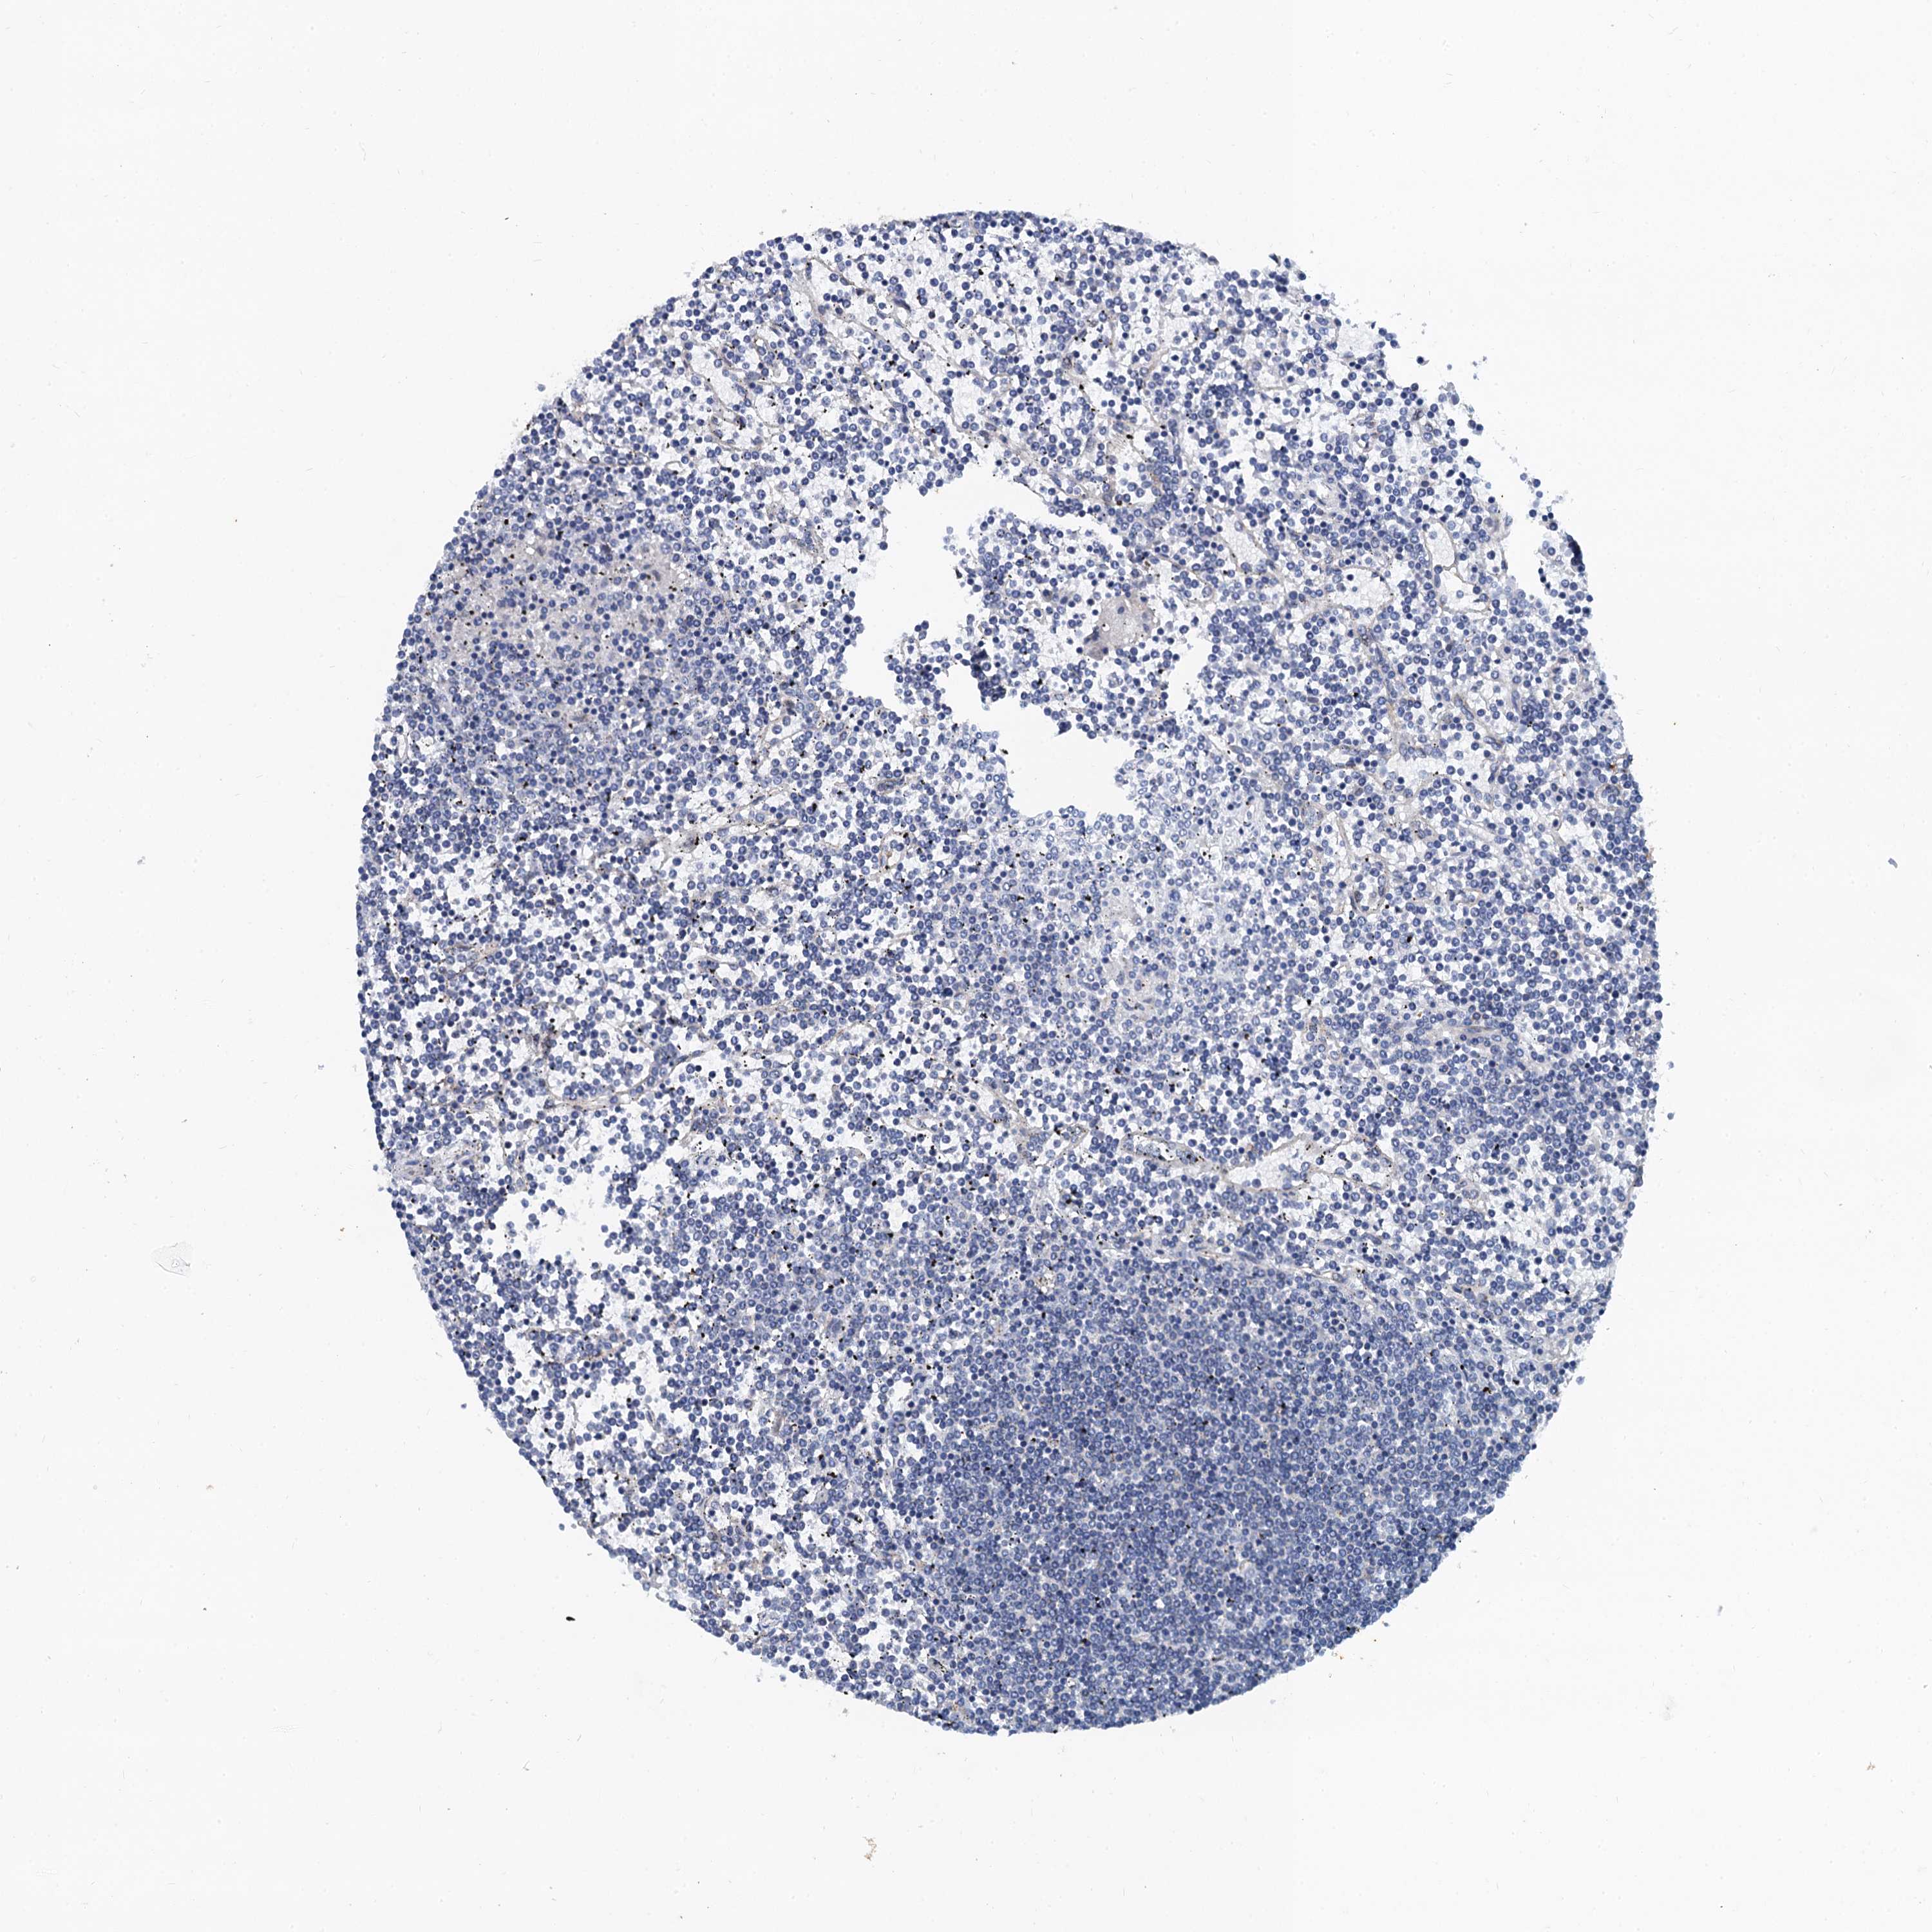

CANCER LYMPHOMA Show tissue menu

LYMPHOMA - Protein expressioni

A mouse-over function shows sample information and annotation data. Click on an image to view it in a full screen mode. Samples can be filtered based on level of antibody staining by selecting one or several of the following categories: high, medium, low and not detected. The assay and annotation is described here.

Each image is clickable and will lead to virtual microscopy that enables deeper exploration of all samples and also displays staining intensity scores, fraction scores and subcellular localization as well as patient and tissue information for each sample.

Antibody HPA041367

Hodgkin's disease, NOS

Malignant lymphoma, non-Hodgkin's type, High grade

Malignant lymphoma, non-Hodgkin's type, Low grade